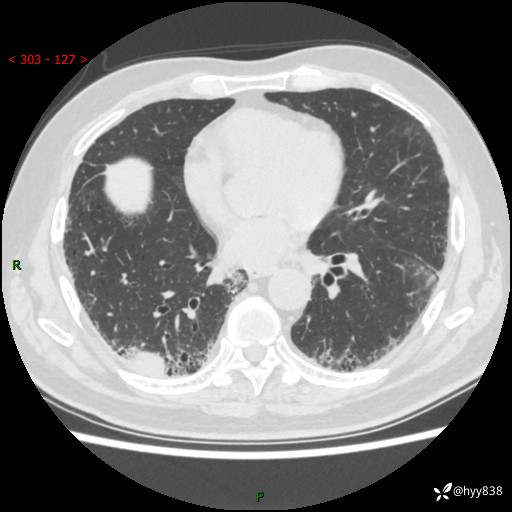

【现病史】:患者半月前无明显诱因出现咳嗽、咳痰,为白色粘痰,无明显加重与缓解因素,伴气促,无发热,无大量脓痰,无胸痛、咯血,无哮鸣音,到我院就诊,胸部CT示右肺结节增大,并口服药物治疗无明显好转,具体用药不详,为求进一步治疗随来我院,经门诊以“孤立性肺结节”收入我科。 病程中患者精神、饮食可,睡眠不佳,大小便正常,体力下降,体重未见明显下降。

【检查】:胸部CT平扫+增强